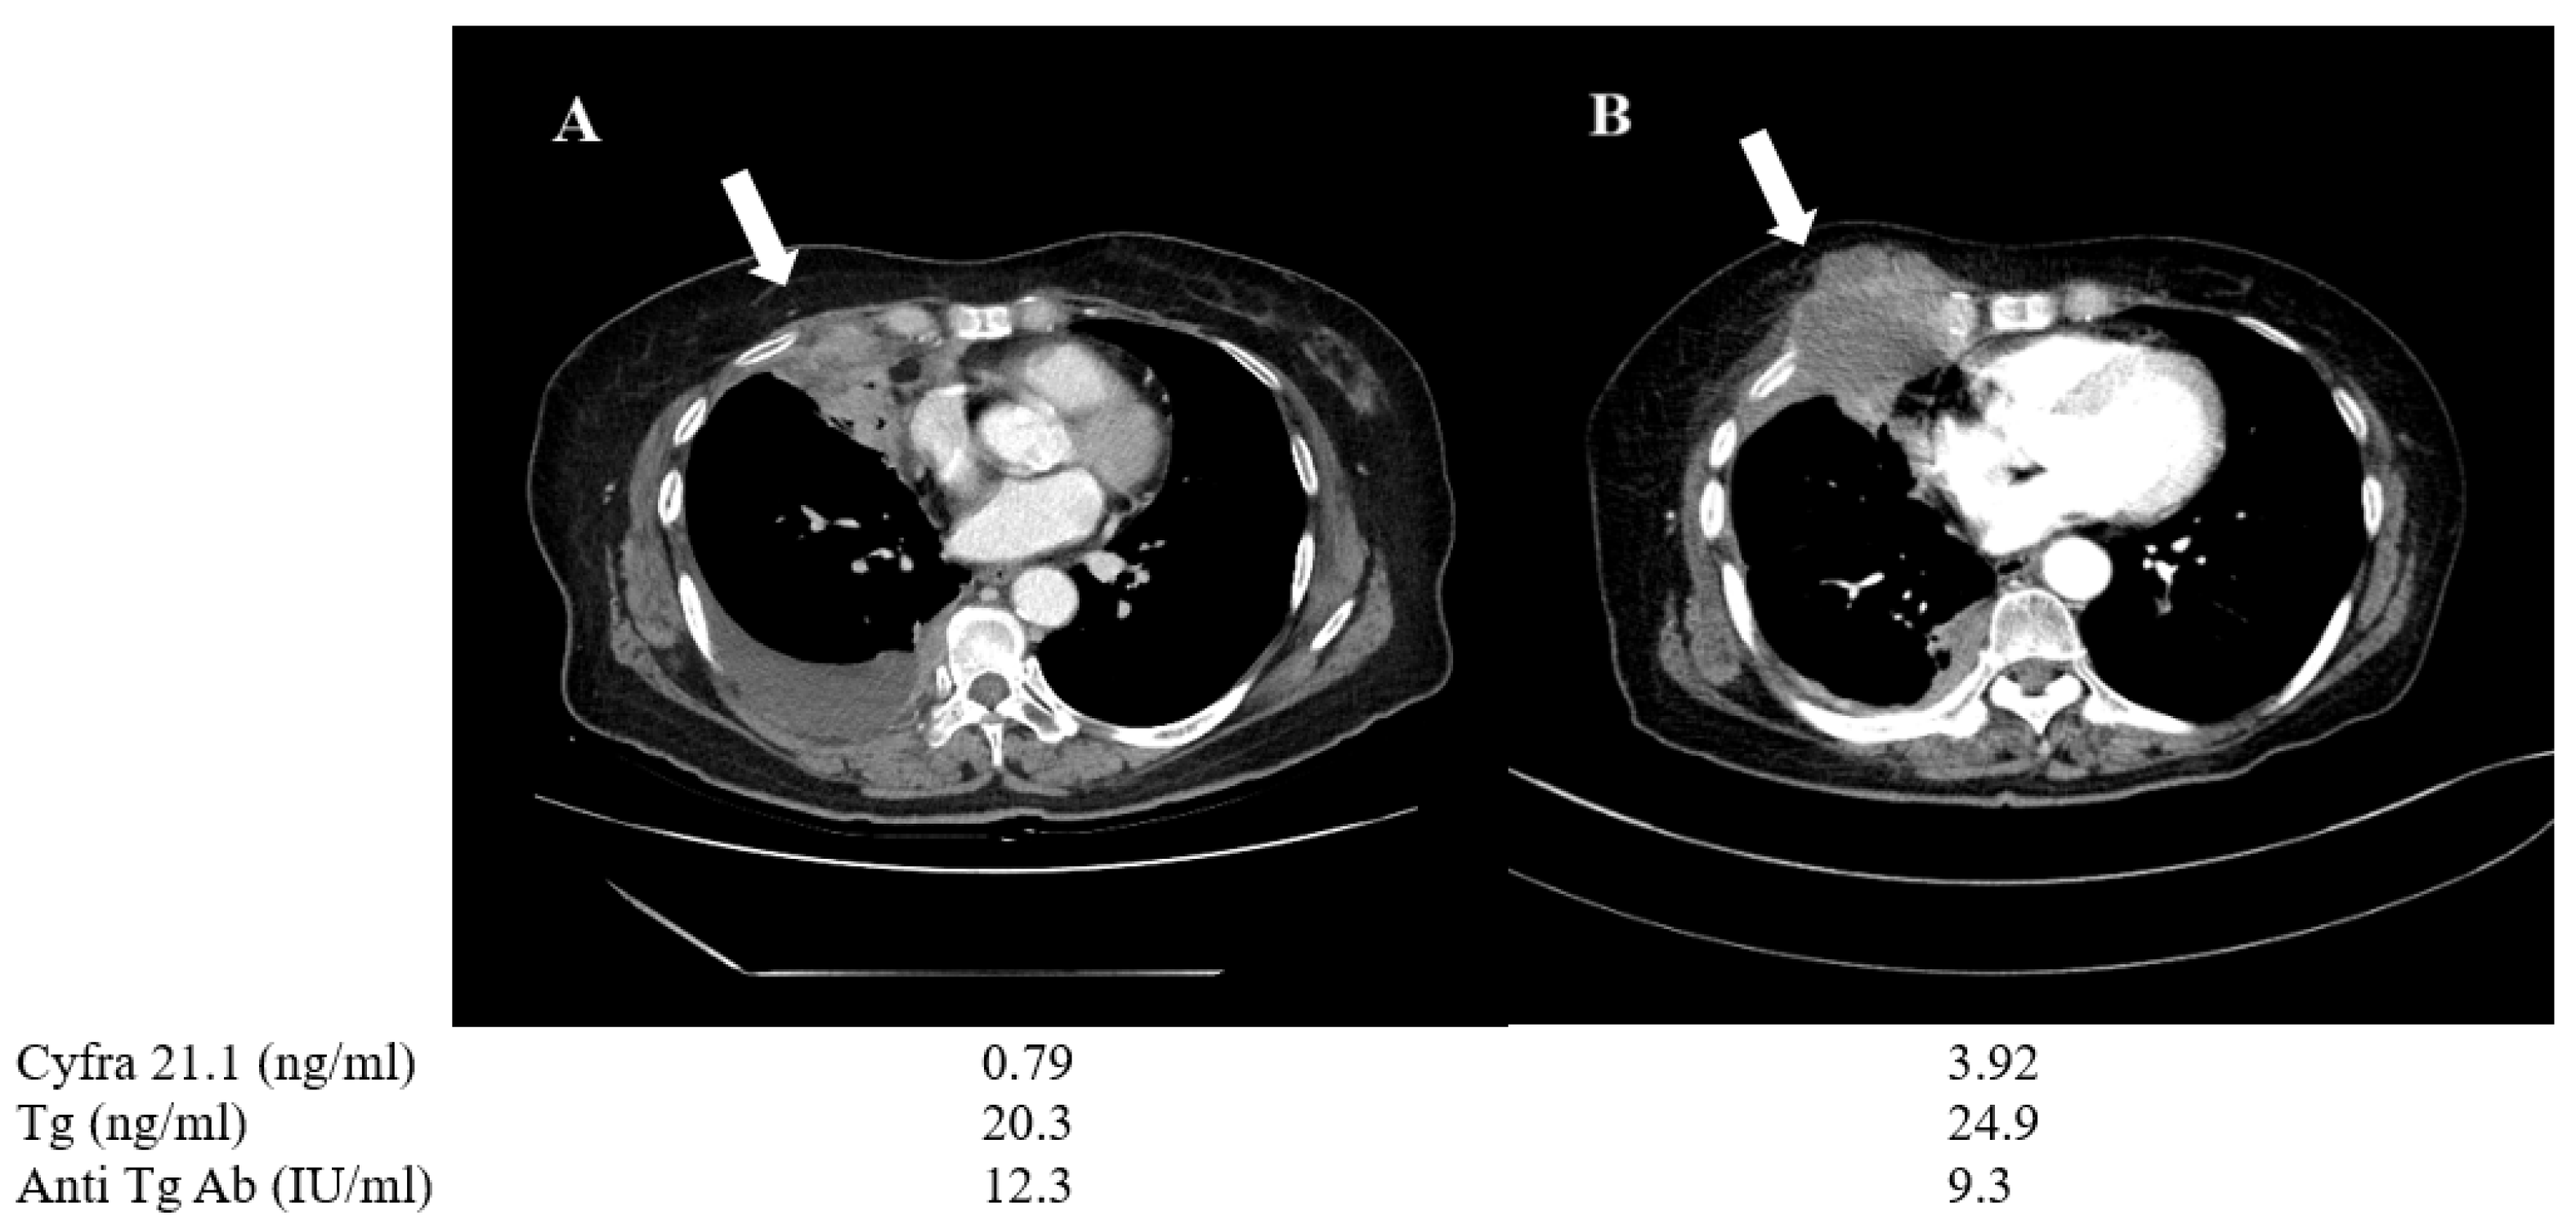

3.4. Representative Patients with Serum Cyfra 21.1 as a Prognostic Biomarker for Disease Progression in Thyroid Cancer

| 6 | F | 70 | PTC > ATC | 20.3 | 24.9 | 0.79 | 3.92 | Lung | Progression/ Change to anaplastic feature | TKI*(LE + SO) |